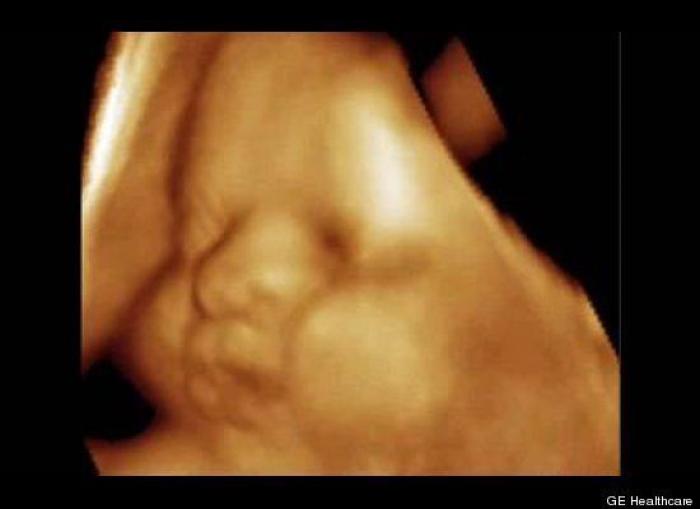

En esta galería puedes ver en fotos como es el desarrollo de un feto de semana en semana:

Desarrollo del feto, en fotos

Ver la galería